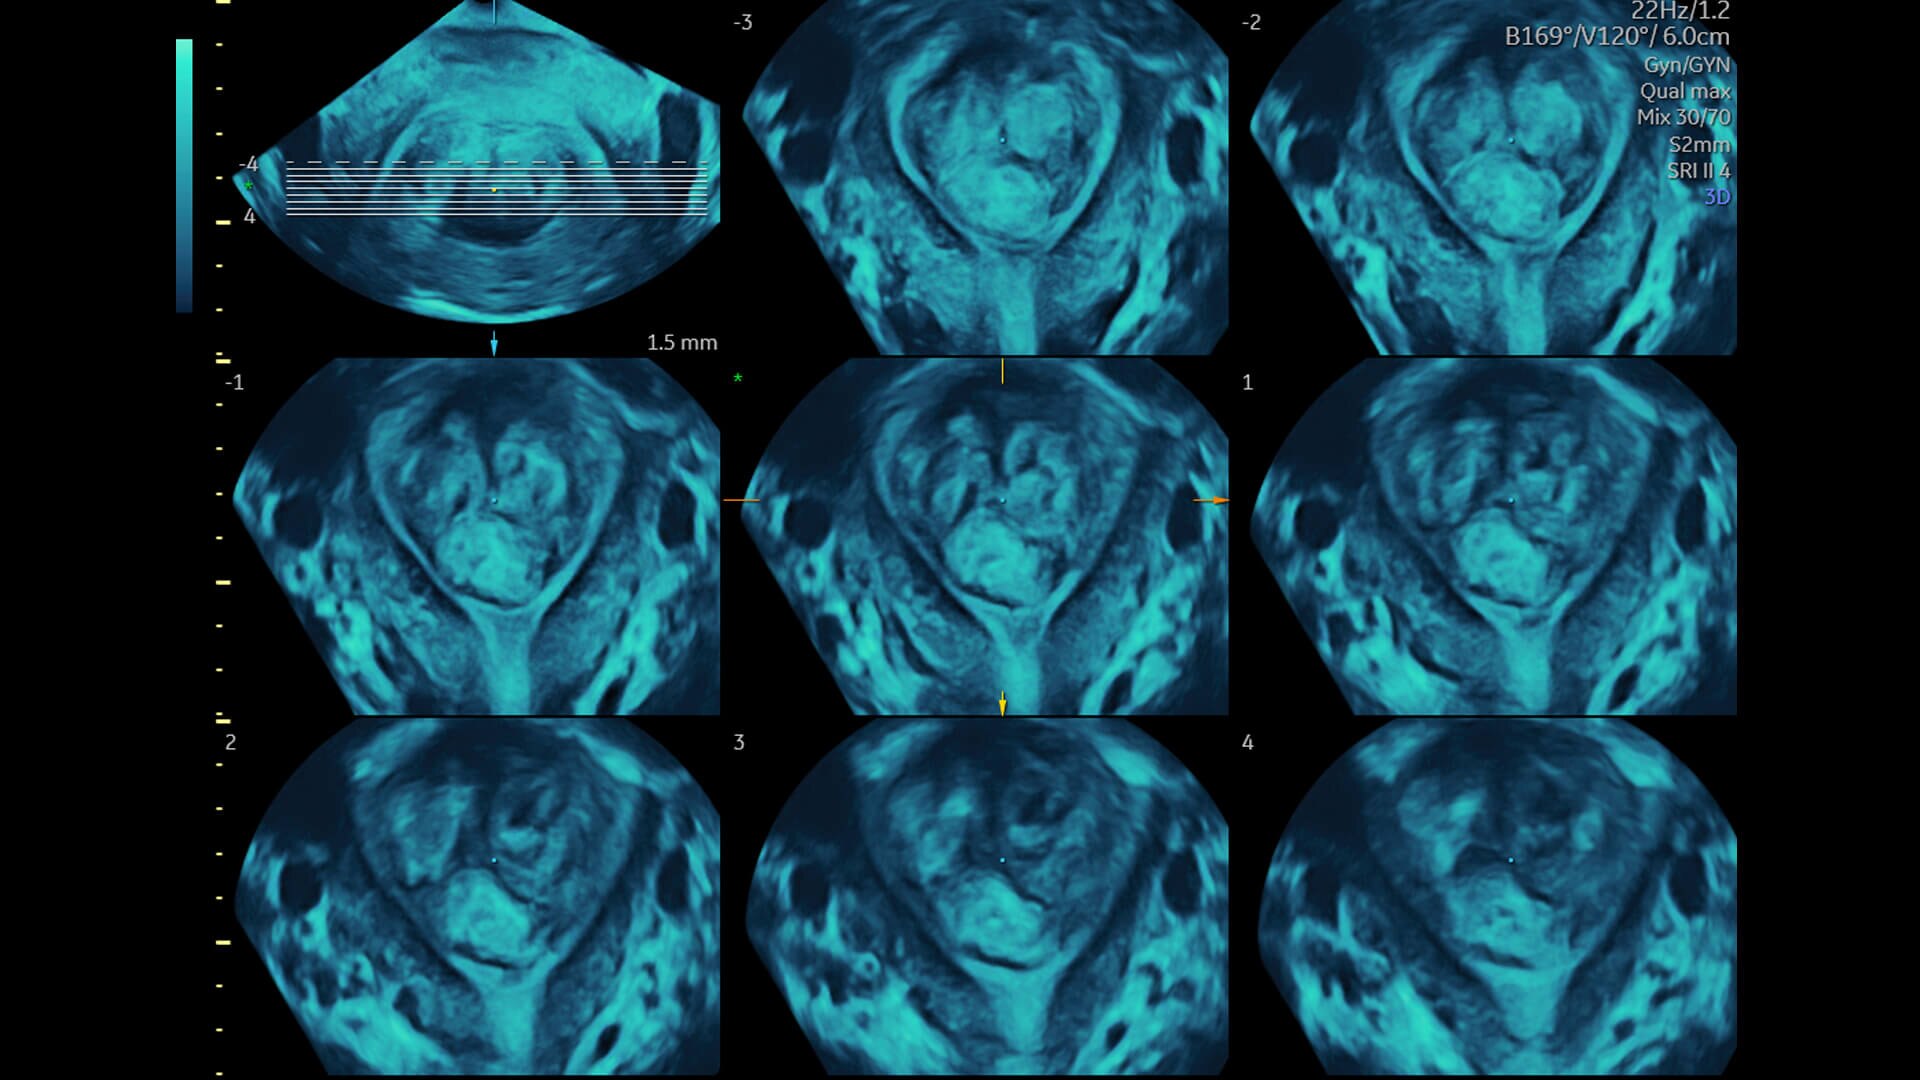

Spine Trace

Welcome to easy 3D in 1/2 the time. Simply trace the spine and the system automatically acquires the volume and displays the coronal view - with 83% less keystrokes.